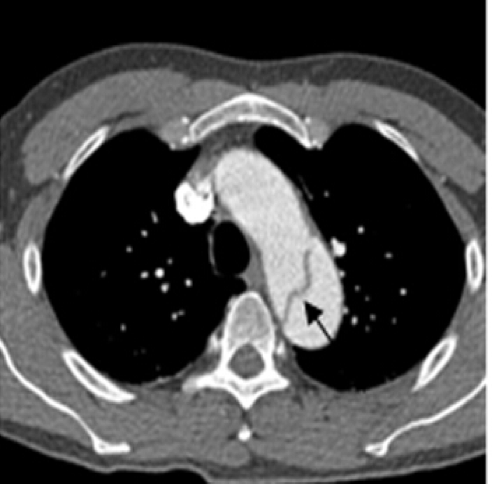

4、主动脉夹层怎么诊断?

突发剧烈胸背痛,特别是伴有血压明显增高者,都需高度警惕主动脉夹层可能。主动脉增强CT是确诊主动脉夹层撕裂的极好方法,且可以迅速完成。

图片 3.png

主动脉CTA

图片 4.png

主动脉CTA明确诊断